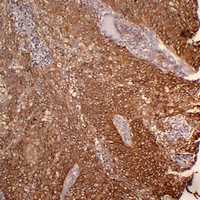

(Immunohistochemical analysis of Cytokeratin 5 staining in human lung squamous cell carcinoma formalin fixed paraffin embedded tissue section. The section was pre-treated using heat mediated antigen retrieval with sodium citrate buffer (pH 6.0). The section was then incubated with the antibody at room temperature and detected using an HRP conjugated compact polymer system. DAB was used as the chromogen. The section was then counterstained with haematoxylin and mounted with DPX.)

(Immunohistochemical analysis of Cytokeratin 5 staining in human squamous cell lung carcinoma formalin fixed paraffin embedded tissue section. The section was pre-treated using heat mediated antigen retrieval with sodium citrate buffer (pH 6.0). The section was then incubated with the antibody at room temperature and detected using an HRP conjugated compact polymer system. DAB was used as the chromogen. The section was then counterstained with haematoxylin and mounted with DPX.)